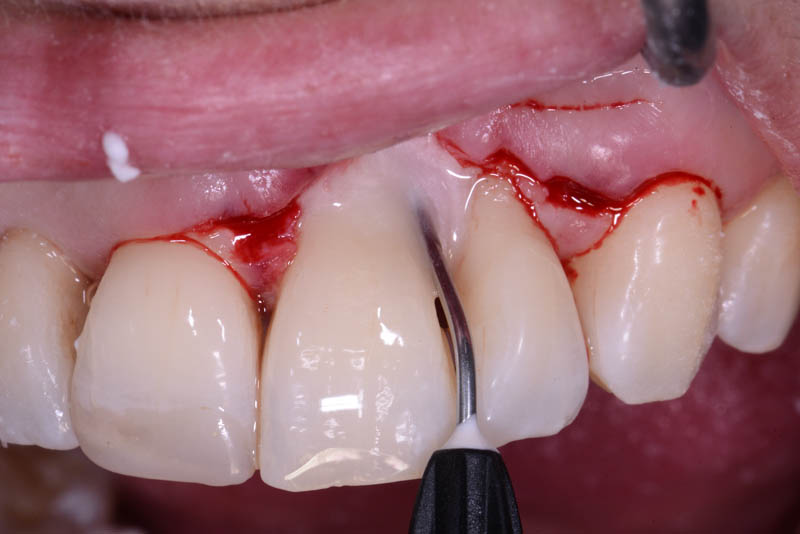

At the end of the orthodontic treatment, a coronally advanced flap was performed according to the De Sanctis and Zucchelli technique, involving papilla preservation and connective tissue grafting, to restore the gingival contour and the papilla between teeth 21 and 22.